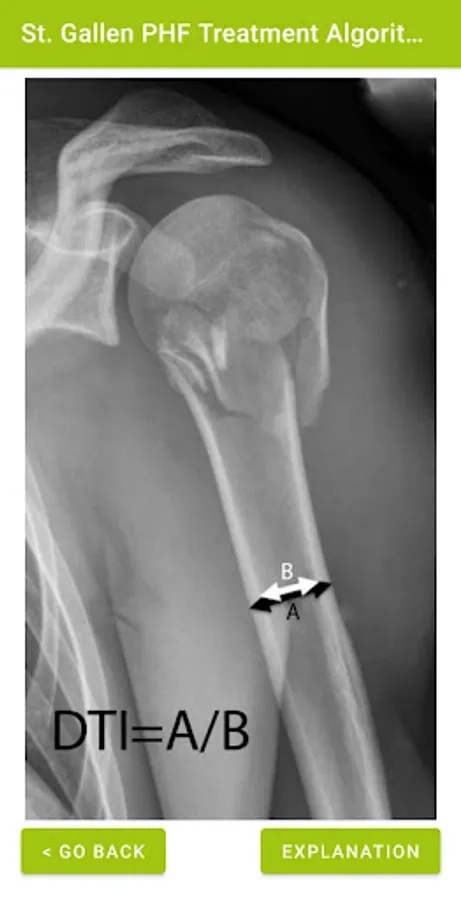

This app was developed by Eng. Laura Scipione and MD Joel Locher to allow reliable, fast and easy application of the St. Gallen proximal humeral fractures treatment algorithm, based on the article "Outcomes of Management of Proximal Humeral Fractures with Patient-Specific, Evidence-Based Treatment Algorithms" published on J Bone Joint Surg Am (doi: 10.2106/JBJS.20.01309) by Prof. B. Jost, PD Dr. C. Spross, MD M. Jacxsens et al.

St. Gallen PHF Algorithm Screenshots